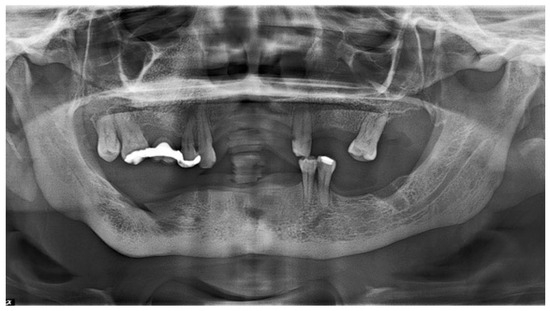

2.1. Examination